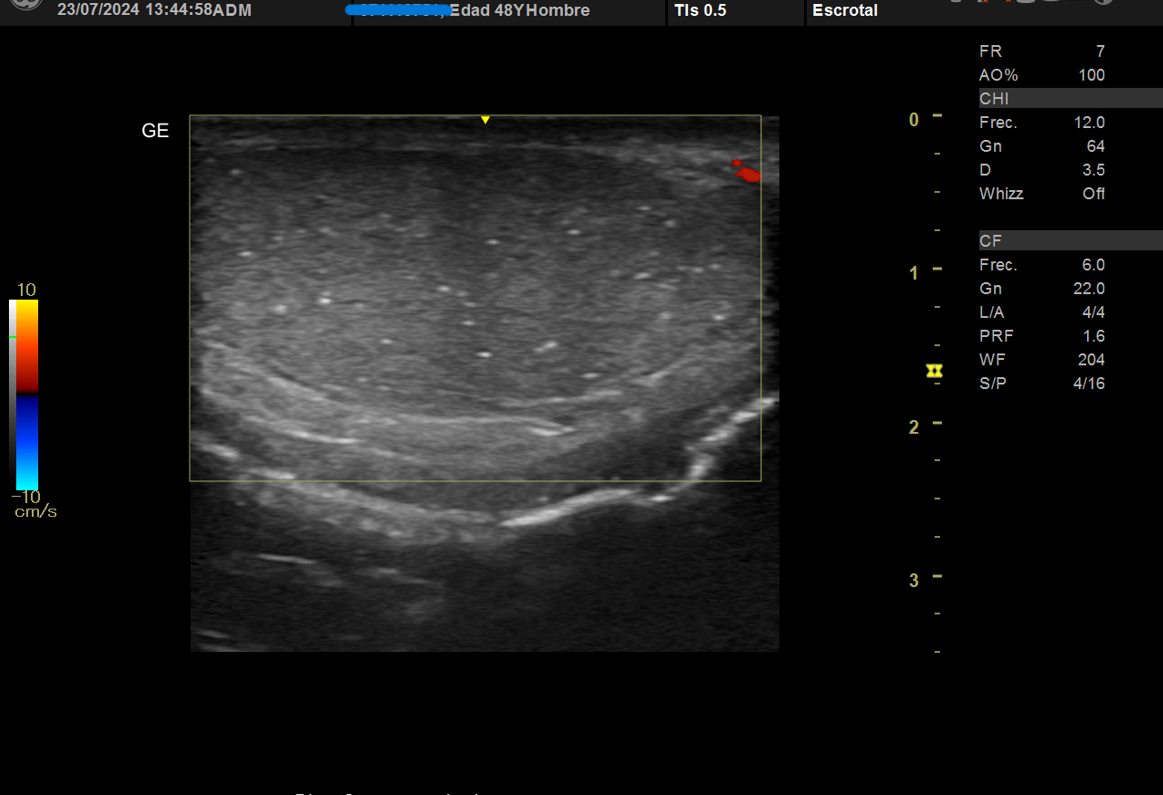

Realizamos ecografía clínica testicular: observamos ambos testículos con microlitiasis bilaterales puntiforme sin sombras acústicasen, en forma de cielo estrellado, vascularización normal, cabeza epidídimo izquierdo con leves signos inflamatorios, mínimo hidrocele.

Se solicita analítica completa con marcador HCG tumoral y LDH normales, serología hepatitis, sida y sífilis negativa, presenta transaminitis, hemograma normal, cultivo orina positivo a Pseudomonas auriginosa.

Inicia tratamiento con cefuroxima 500 mg cada 12 horas, se solicita analítica completa con marcador HCG tumoral y LDH normales, serología hepatitis, sida y sífilis negativa, transaminitis, hemograma normal, cultivo orina positivo a Pseudomonas auriginosa. Ecografía testicular reglada testicular preferente que es realizada al mes con mejoría de orquiepidimitis y confirma microlitiasis testiculares.